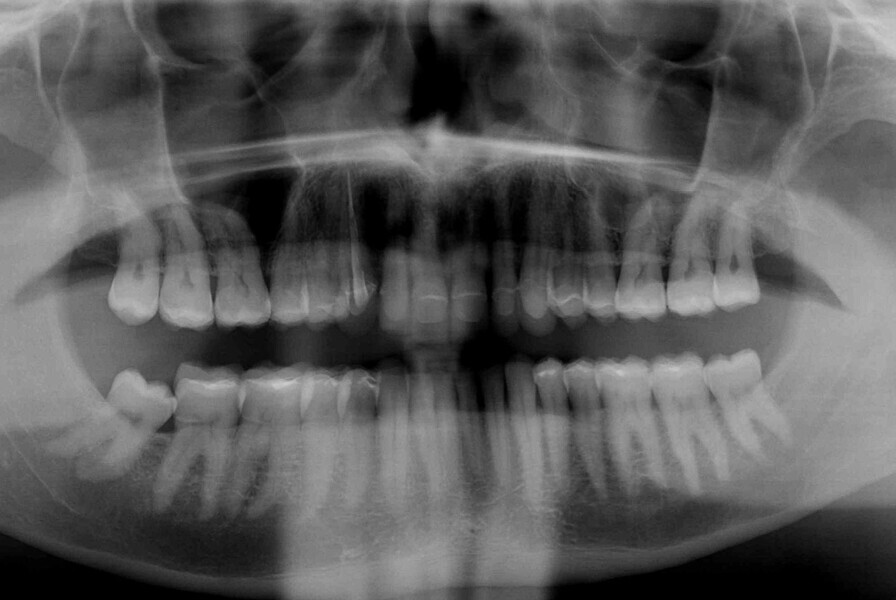

Fig. 4: Initial situation, panoramic radiograph (2015).